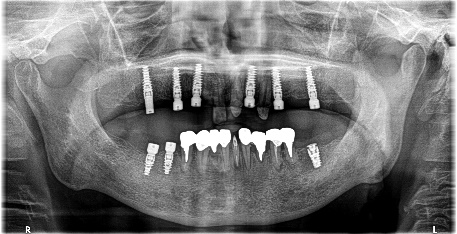

上顎4本残っている歯を抜歯し、インプラントを6本埋入。下顎、右下2本、左下1本埋入。

上顎3本は、もし義歯で対応する場合であれば、保存してマグネット義歯の支台として活用します。しかし、患者さんが義歯ではなくインプラント治療を希望され、かつ、見た目が自然でよく嚙めるようになることが最優先事項でしたので、相談したうえで3本の歯は積極的に抜歯しました。

治療後、「インプラント治療に満足しています。食事が楽しくなりました。スタッフの方の説明がわかりやすかったです。1年間ありがとうございました。」と、とてもうれしくなる感想を書いていただきました。

Before

After